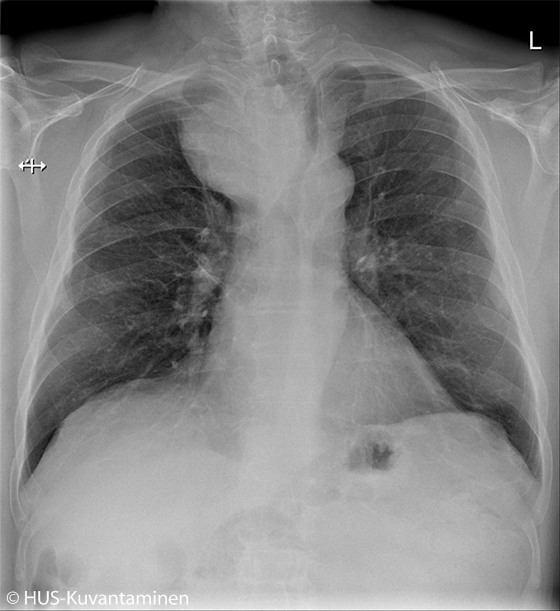

Kookas struumakyhmy keuhkokuvassa.

Potilaan keuhkokuva tarkistettiin pitkittyneen flunssan vuoksi. Oireita selittävää syytä ei löytynyt, mutta kuvassa näkyy ylämediastinumin massa, jonka vuoksi trakea devioi vasemmalle. Keuhkokudoksessa ei ole aktuellia ja hilusalueet sekä keuhkosopet ovat siistit. Kuvan löydös oli aihe jatkotutkimuksille. Ultraäänitutkimuksessa todettiin retrosternaalisesti ulottuva kookas oikea kilpirauhaslohko, joksi thoraxkuvan muutoskin sopii.